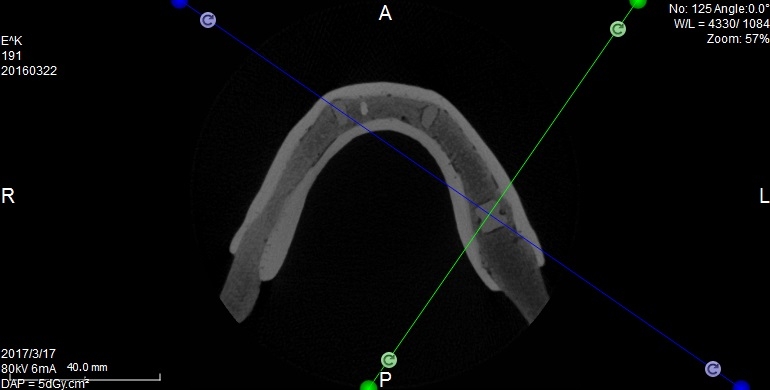

Oferujemy również szablony chirurgiczne przeznaczone do szkoleń z implantacji. Umożliwiają planowanie leczenia implantologicznego i przeprowadzenie szkoleń z wykorzystaniem plików CT, STL oraz druku 3D. Oferujemy nasze modele do szkoleń implantologicznych wraz z plikami DICOM i STL.

Pliki do wykonania szablonów można pobrać z naszej strony internetowej. Możemy je również dostarczyć wraz z modelami. Pliki te dostępne są dla modeli 10-1030, 10-3040, 10-3050, 10-5070,